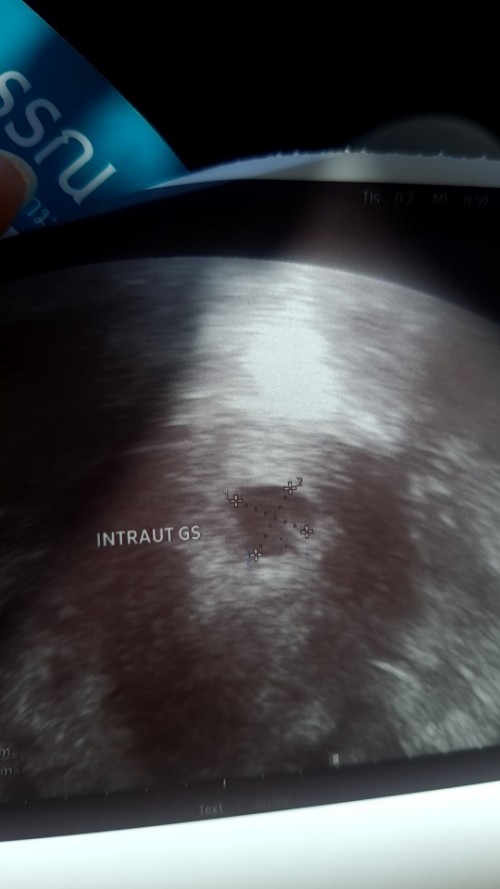

ตั้งครรภ์ 6 สัปดาห์ค่ะ คุณหมอนัดซาวเจอถุงตั้งครรภ์ แต่ยังไม่เห็นตัวเด็ก คุณหมอบอกว่าเห็นถุงไข่แดงข้างใน ตอนนี้แม่เครียดกลัวเปนท้องลม ตอนแม่ๆ6สัปดาห์ ซาวเปนแบบไหนกันบ้างคะ

ของเราไปตรวจมาวันนี้น้องได้6สัปดาห์คะ น้องอาจจะยังเล็กนะคะแม่ บ้างคนเจอตอน10วิค ก็มีคะ